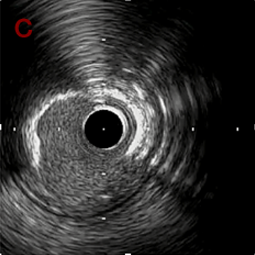

IVUS after OAS low speed 3回

IVUS imaging after low speed 3回

OAS low speedによる引きのsandingを3回行いIVUSを確認するとa-cでは心筋側側へのOASによる良好なbias変化と、それに伴いdの健常側への危険なbias変化を認めた。

そのためcでIVUSマーキングを行い、その点より引きで赤線のpinpoint OAS high speedを行い、dに関してはinjury回避のためにOASを当てない方針とした。